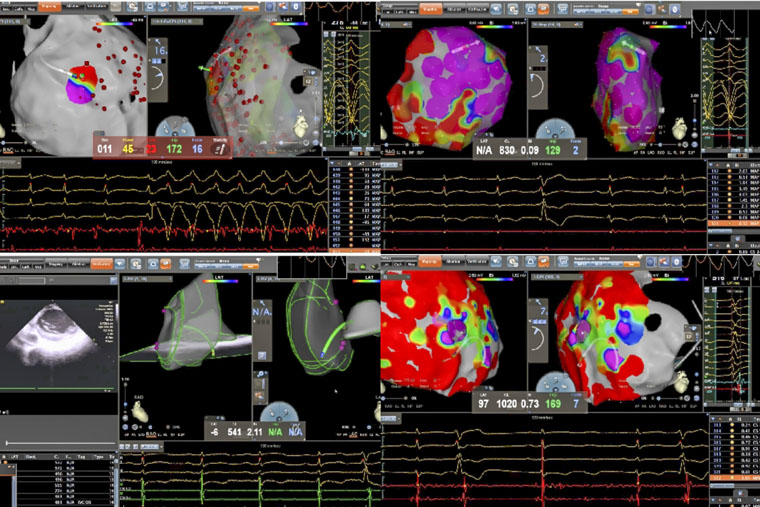

近日,我院心血管内科在马景涛副院长、姚铁柱副主任的指导下,连续完成两例高难度射频消融手术。一例为致心律失常性右室心肌病(ARVC)导致的顽固性病理性室速,另一例为合并贲门癌的左室乳头肌室早消融。两例手术的成功,不仅标志着我院在器质性心脏病相关室性心律失常介入治疗领域实现进一步突破,也突显了多学科协作(MDT)模式在处理复杂危重症患者中的重要价值。

病理性室速通常指由器质性心脏病(如心肌梗死、心肌病等)所导致的室性心动过速。一名患者所患的ARVC,是一种以右心室心肌被纤维脂肪组织替代为特征的遗传性疾病,异常的心肌结构易形成异常电传导通路,从而引发药物难以控制的恶性室速,传统治疗难度大、复发率高。术中,手术团队在X线透视引导下施行心包穿刺,有效规避冠状动脉及心肌损伤风险,为心外膜途径消融建立安全通道。在此基础上,同步进行心内膜及心外膜高密度标测,于右心室多部位识别出低电压区、延迟电位等异常电活动特征,精准判定参与心动过速的关键区域,依托三维电生理标测系统,完成了心内膜与心外膜联合消融。

另一名患者为61岁男性,术前发现频发室性早搏(24小时超过10930次),部分呈三联律及短阵室速,心电图提示起源点为左室乳头肌。频发室早对即将接受大型癌症手术的患者构成多重威胁,如麻醉可能诱发恶性心律失常、室早会影响血流动力学稳定、心脏问题还可能延误肿瘤手术时机。心内科与胃肠外科、麻醉科迅速启动MDT讨论,一致认为必须在肿瘤手术前根除室早这一“定时炸弹”。团队即刻启用“电生理第三只眼”——心腔内超声(ICE)引导手术:ICE导管送入心腔,实时显示左室内乳头肌形态、位置及导管贴靠情况;在ICE引导下克服乳头肌移动难题,实现稳定贴靠与精准消融;ICE实时监测心包情况,极大避免并发症的发生。术后患者室早完全消失,心脏风险解除,并于次日顺利接受贲门癌根治术,现已康复出院。

姚铁柱副主任表示,两例手术的成功实施,共同依托于术前的充分评估与个体化方案设计先进的影像引导技术(X线、三维标测、ICE)以及手术团队娴熟的技术配合与对心律失常机制的深刻理解。

器质性室速与复杂结构起源室早的消融,是心脏电生理领域的重要挑战。联合心内膜与心外膜途径的标测与消融,以及ICE引导下的精准操作,可显著提高此类复杂心律失常的治愈率,为药物无效、常规消融困难或合并多系统疾病的患者提供新的治疗途径。